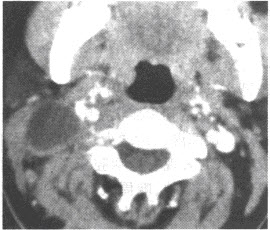

患者,男性,79岁,上腹部疼痛,不易缓解,吐咖啡色血液。行上腹部CT增强扫描,如下图